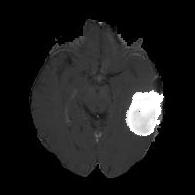

(a) (b) (c) (d)

Boundary Stream:

Fig. 2 demonstrates the output of each of the attention layers in our dedicated boundary stream. In essence, each attention layer progressively localizes the tumor and refines the boundaries. The first attention layer has learned rough estimate of the boundaries around the tumor and localized it, whereas the second and third layers have learned more fine-grained details of the edges and boundaries, refining the localization. Moreover, since our architecture leverages a dilated spatial pyramid pooling to merge the learned feature maps of the regular segmentation stream and the boundary stream, multiscale regional and boundary information have been preserved and fused properly, which has enabled our network to capture the small structural details of the tumor.